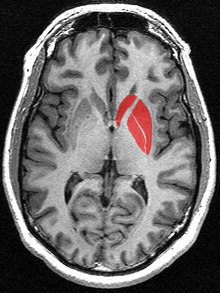

The striatum, also known as the neostriatum or striate nucleus, is a subcortical part of the forebrain and a critical component of the reward system. It receives glutamatergic and dopaminergic inputs from different sources and serves as the primary input to the rest of the basal ganglia system. In all primates, the dorsal striatum is divided by a white matter tract called the internal capsule into two sectors called the caudate nucleus and the putamen.[4] The ventral striatum is composed of the nucleus accumbens and olfactory tubercle in primates.[4] Functionally, the striatum coordinates multiple aspects of cognition, including motor and action planning, decision-making, motivation, reinforcement, and reward perception.[2][3][4]

The striatum is divided into ventral and dorsal subregions, based upon function and connectivity. The ventral striatum is composed of the nucleus accumbens and olfactory tubercle, whereas the dorsal striatum is composed of the caudate nucleus and putamen.